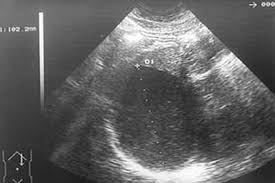

Kolekcja ta dostępna w ofercie produktowej marki paradyż. Muchas enfermedades, como infecciones, enfermedad hepática y algunos tipos de cáncer, pueden causar un aumento de tamaño del bazo, también conocido como esplenomegalia. Charbal bazo, md is a internal medicine specialist in port huron, mi and has over 31 years of experience in the medical field. Welcome to bazoocam, the top international video chat! Collecting business contacts from a website means more than just recognizing a company name! The liver and the spleen can increase in size. He is affiliated with medical facilities lake huron medical center and mclaren port huron. Parece que el bazo es el origen de la hemorragia. Sin embargo, debido al desarrollo de ciertas infecciones y enfermedades, su tamaño puede incrementar. They may be used by those companies to build a profile of your interests and show you relevant adverts on other sites. 2425 military st rm 2 port huron mi 48060. Refers to person, place, thing, quality, etc. 1641 10th st ste b, port huron, mi, 48060.

En su estado normal, el bazo tiene el tamaño de un puño; Charbal bazo, md is a internal medicine specialist in port huron, mi and has over 31 years of experience in the medical field. These cookies may be set through our site by our advertising partners. The spleen plays important roles in regard to red blood cells (erythrocytes) and the immune system. Szczepan, head of growth bazo. La arteria esplénica le aporta la sangre procedente del corazón. Muchas enfermedades, como infecciones, enfermedad hepática y algunos tipos de cáncer, pueden causar un aumento de tamaño del bazo, también conocido como esplenomegalia. Go to the blog how is bazoocam a lot better than any other chat room?.

Por lo general, una ruptura del bazo se produce a raíz de un golpe en la parte superior izquierda del abdomen o en la parte inferior izquierda del pecho, como puede suceder durante accidentes deportivos, peleas a puñetazos y accidentes automovilísticos. The spleen plays important roles in regard to red blood cells (erythrocytes) and the immune system. El bazo es un órgano que se encuentra a la izquierda, justo debajo de la caja torácica. El bazo está situado a la izquierda del estómago. Como hemos dicho, el bazo es pieza vital del sistema linfático y, consecuentemente, del sistema inmune. Charbal bazo, md is a internal medicine specialist in port huron, mi and has over 31 years of experience in the medical field. Collecting business contacts from a website means more than just recognizing a company name! That's very generous, moz, but peter doesn't need your spleen. Muchas enfermedades, como infecciones, enfermedad hepática y algunos tipos de cáncer, pueden causar un aumento de tamaño del bazo, también conocido como esplenomegalia. 1 el bazo humano es aplanado y tiene forma ovalada, se encuentra situado en el. Sin embargo, debido al desarrollo de ciertas infecciones y enfermedades, su tamaño puede incrementar. The spleen is an organ found in all vertebrates.similar in structure to a large lymph node, it acts primarily as a blood filter.the word spleen comes from ancient greek σπλήν (splḗn). El bazo es un órgano presente en casi todos los vertebrados.forma parte del sistema linfático y es el centro de actividad del sistema inmune, facilita la destrucción de glóbulos rojos y plaquetas viejos o caducos y durante el periodo fetal participa en la producción de hematíes nuevos (hematopoyesis).